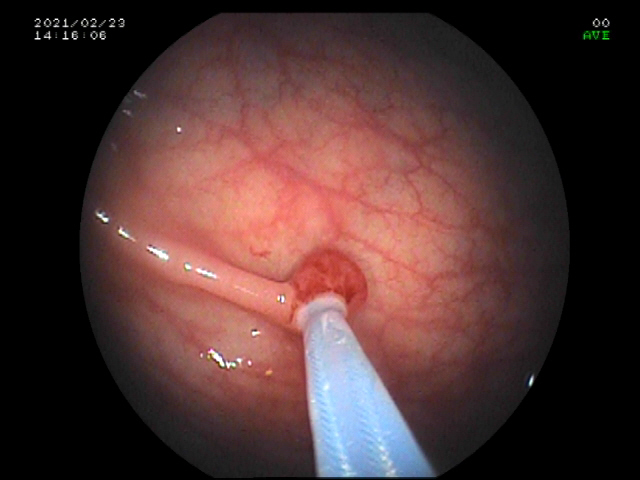

微小及小息肉是结肠镜检最常见的息肉。我院在省内较早开展内镜下结直肠息肉冷切除术,该技术的适应证是结直肠小息肉及微小息肉,对于大小为1-3mm的微小息肉用活检钳直接钳除,对于大小为4-9mm的无蒂息肉应用圈套器勒除。

圈套器切除息肉

内镜下结直肠息肉冷切除术同目前主流的电切除术最大的区别是冷切除,不应用高频电,故可有效避免高频电相关的电损伤、迟发性穿孔、迟发性出血等并发症。而且冷切除术简单高效,使用器械较少,基本使用一把圈套器就可完成内镜下息肉切除术,而目前主流的内镜下电切除术需要用内镜注射针、热活检钳,往往还需要钛夹夹闭创面,相比较冷切除术不但操作时间短,可有效减少医用耗材的支出,而且术后并发症低。因此,内镜下结直肠息肉冷切除术可以广泛地用于结肠息肉筛查,有助于降低结肠癌的发病率,造福于广大患者。